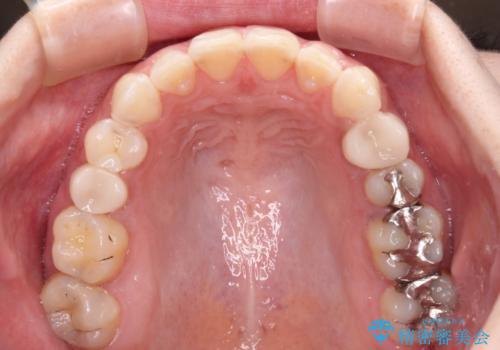

- 前歯の歯列不正を気にして来院された患者様です。

インビザラインでの矯正治療を希望されていましたが、奥歯の咬み合わせがインビザライン単独では改善困難と判断されたので、補助装置を併用することとしました。

まずは裏側の装置やワイヤー矯正を用いて歯列幅の狭い上顎を側方に拡大しつつ全体を後方に移動させ、その後インビザラインにて歯列を整えることとしました。